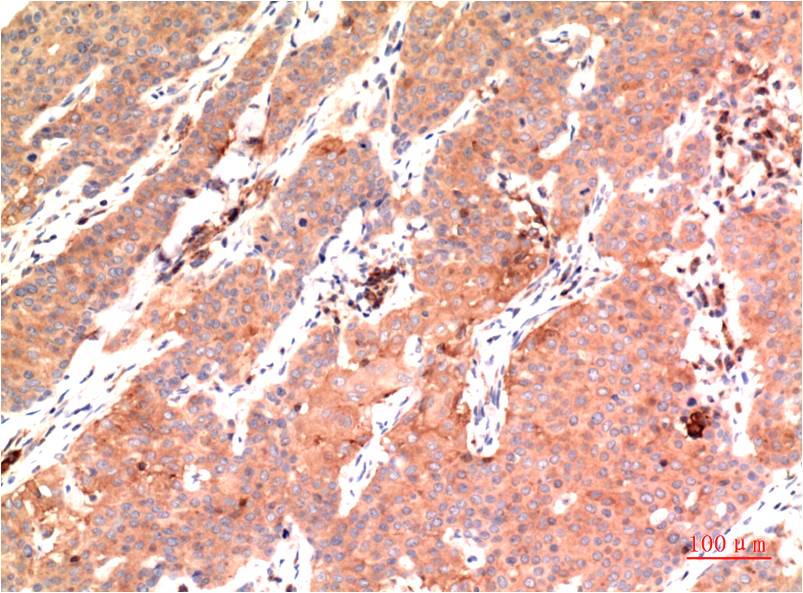

Immunohistochemical analysis of paraffin-embedded Human Breast Carcinoma Tissue using?Epsilon Tubulin(EM1311 )Mouse mAb diluted at 1:200.